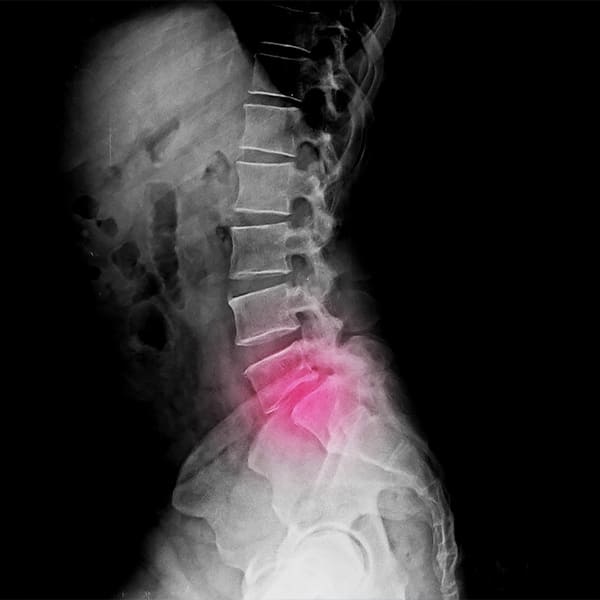

Patologías de columna

Con frecuencia, las enfermedades de la columna provocan dolor cuando los cambios óseos presionan la médula o los nervios. También pueden limitar el movimiento. El tratamiento varía según la enfermedad, pero algunas veces incluyen aparatos ortopédicos para la espalda y cirugía.

Cirugías de columna

La cirugía de columna permite descomprimir, movilizar los elementos, fijar estructuras vertebrales y sustituirlos. La cirugía de la espalda es una opción a tener en cuenta en el momento en el que tratamientos conservadores no han funcionado y el dolor sigue siendo persistente e impide el desarrollo de una vida normal. Existen diversos tipos de cirugía de espalda: